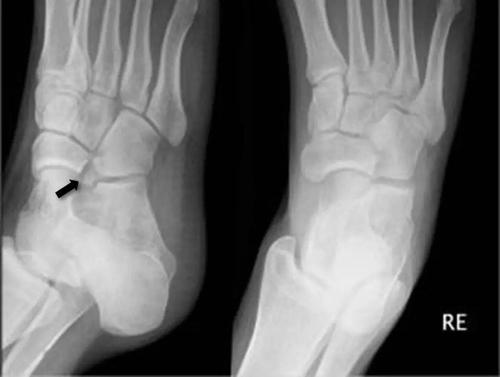

足踝撕脱性骨折与籽骨分不清楚?背下这张图再也不会漏

籽骨骨折